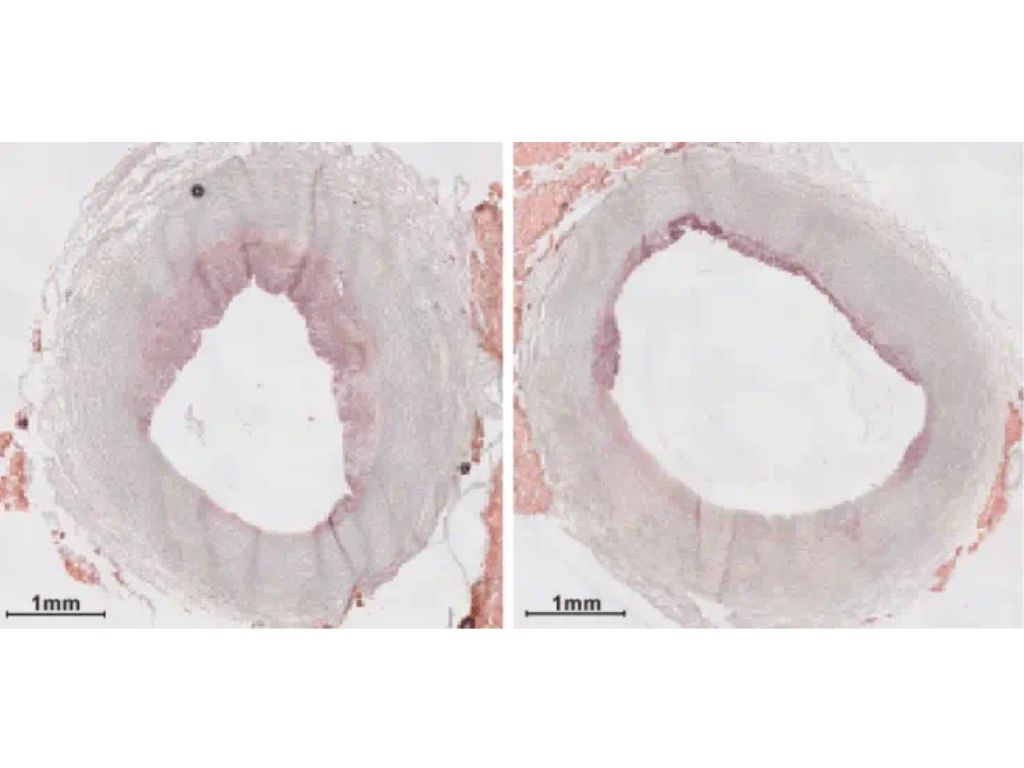

The team successfully tested the infusion on pig models, showing reduced artery inflammation without side effects. This in itself is a major achievement for future human trials, bringing us one step closer to safer, more precise cardiovascular therapies. Treating highly inflammatory plaque is key - it can rupture without warning, causing sudden and severe heart attacks. As Smith explained, this type of plaque poses a greater threat because it may not cause visible blockages but can lead to fatal consequences.